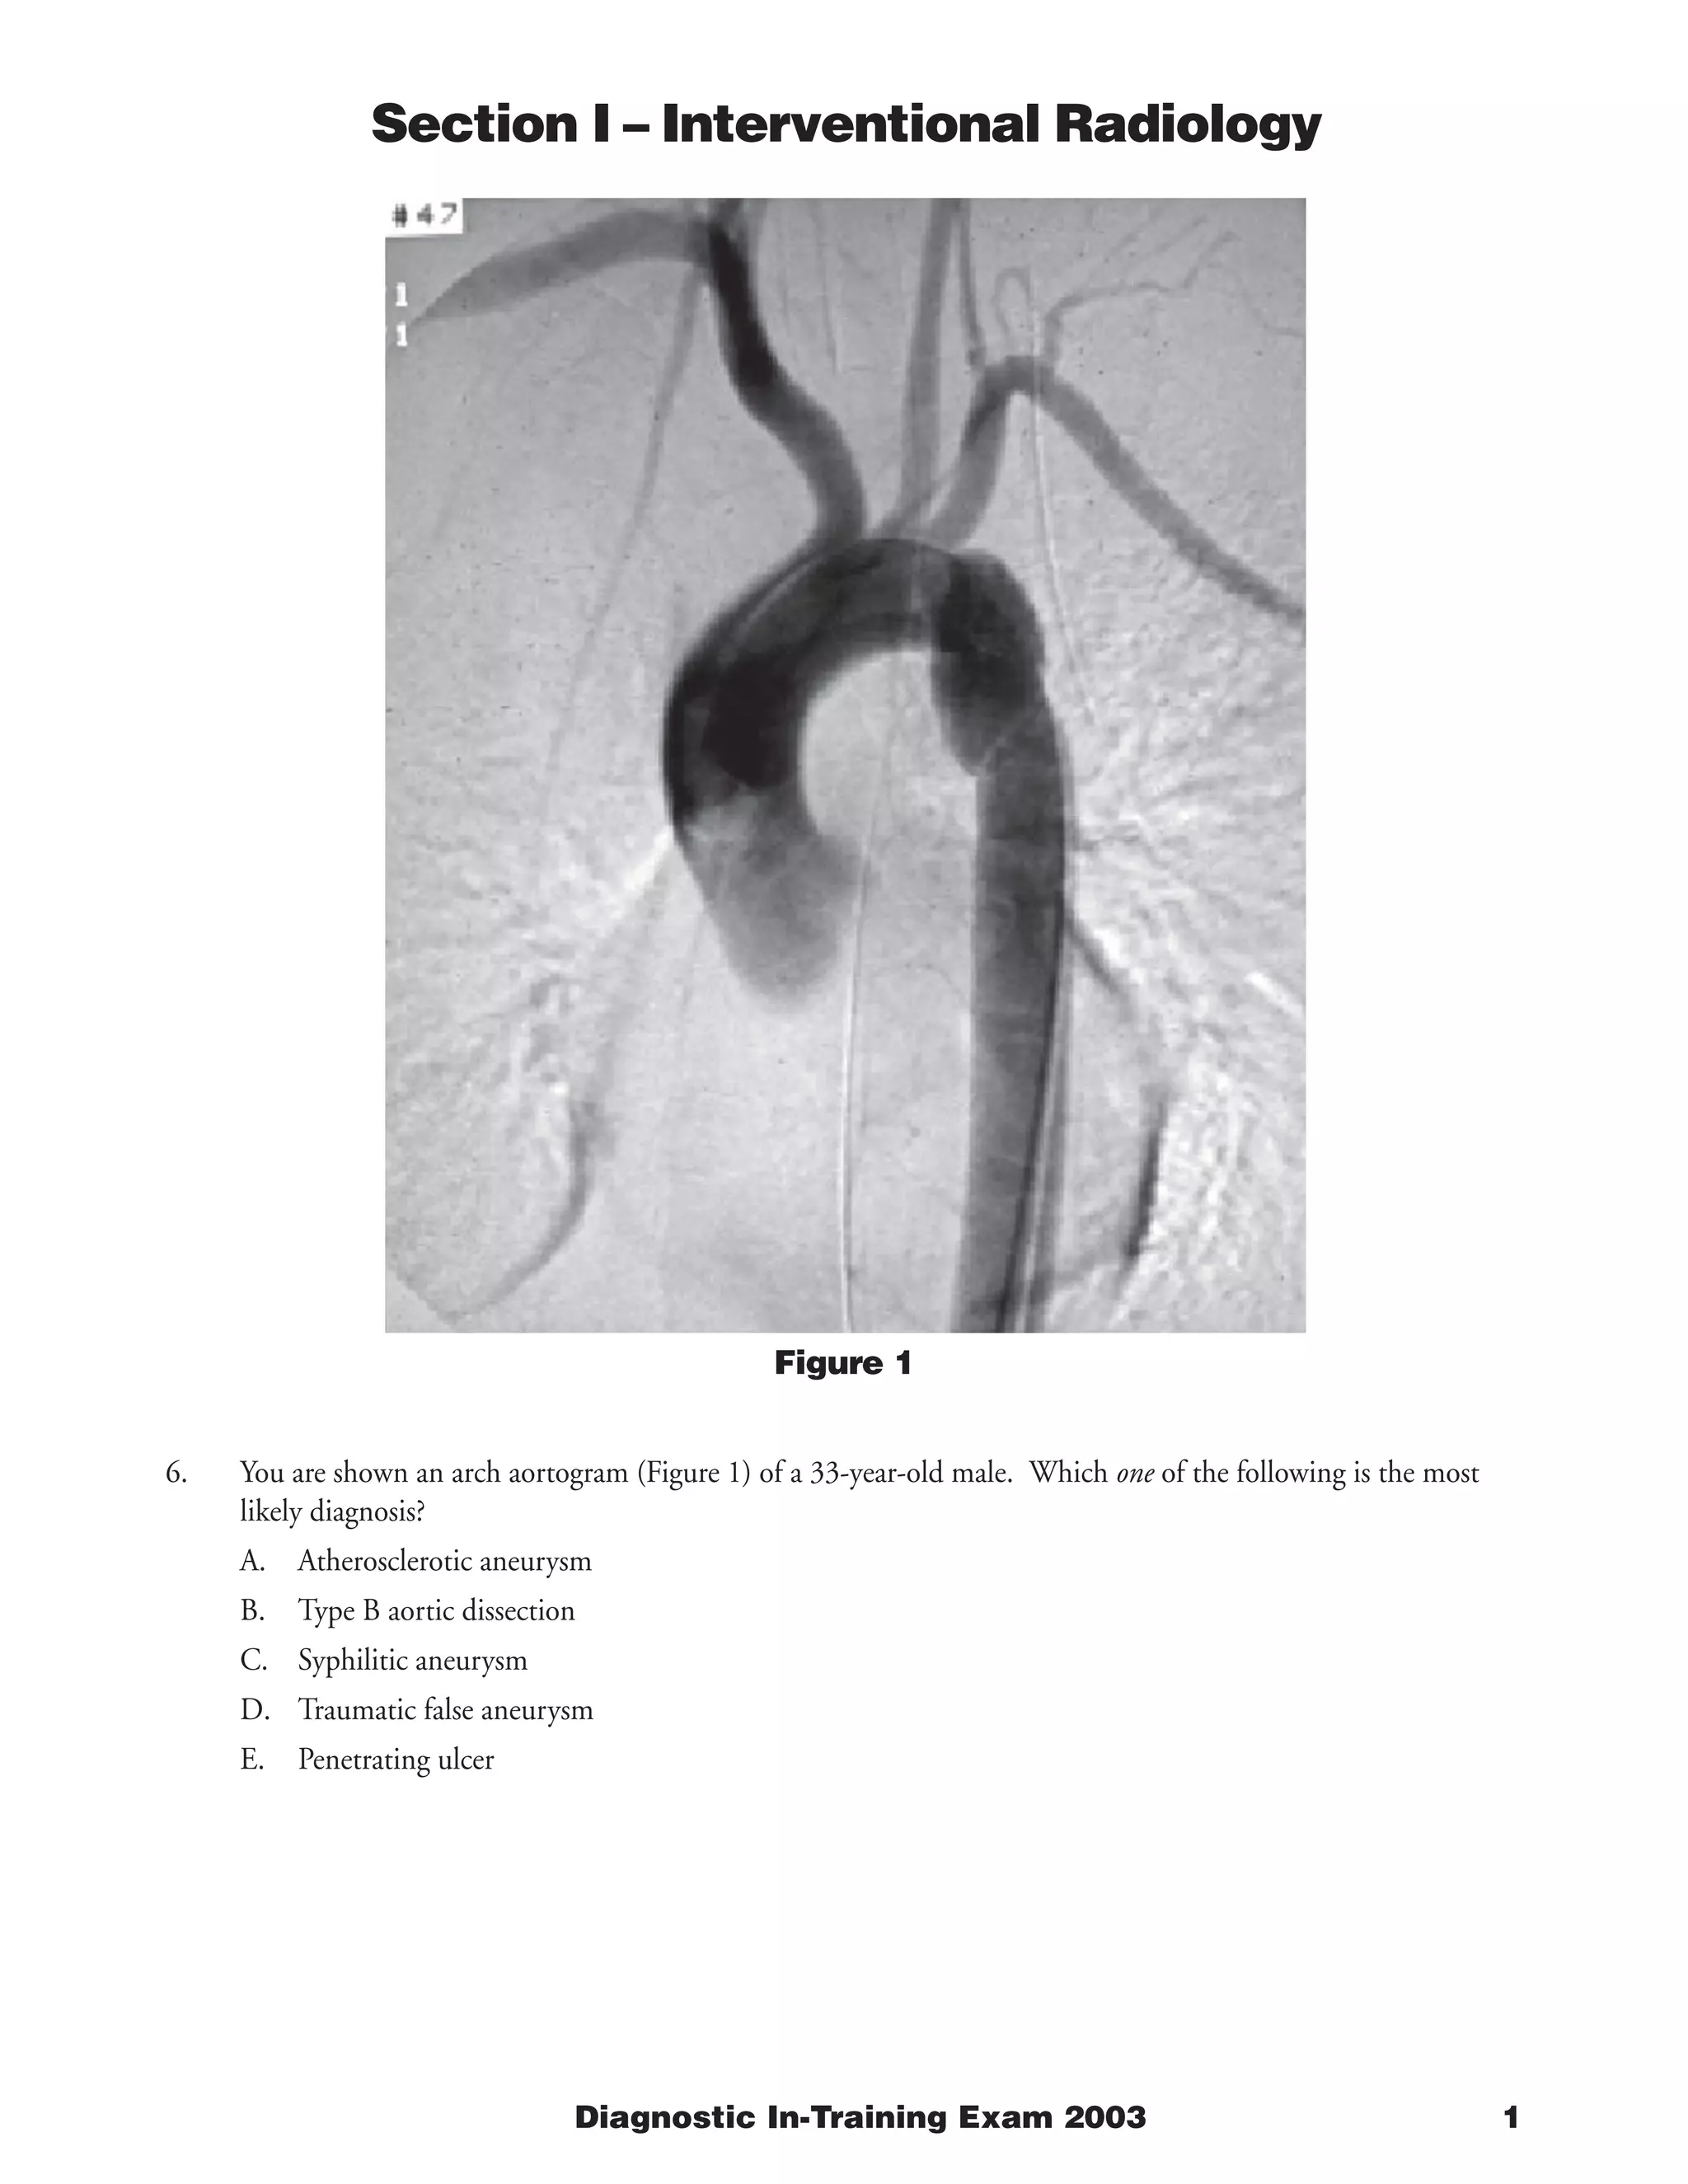

The document describes a case involving a chest x-ray and pulmonary angiogram findings in a 57-year-old female patient who presented with chest pain two weeks following a hemorrhagic stroke. The pulmonary angiogram shows multiple filling defects in the left main pulmonary artery and its branches, consistent with pulmonary embolism. While anticoagulation is usually the standard therapy for pulmonary embolism, it is contraindicated in this patient due to her recent stroke. Therefore, the best management option is placement of an inferior vena cava filter to prevent further pulmonary emboli while existing clots dissolve, as anticoagulation cannot be used due to her recent hemorrhagic stroke.